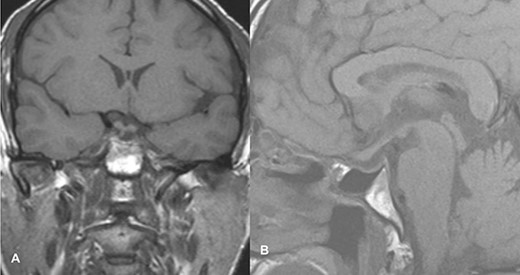

PA was diagnosed when radiographic findings showed acute pituitary hemorrhage and subsequent pituitary adenectomy was planned, but surgery was delayed up to 13 days because of non-critical coronary artery disease detected on coronary angiography. When his condition stabilized, he underwent surgery. The tumor was soft to firm and a safe maximal resection was performed. Hemostasis was achieved and sella packed with fat harvested from the subcutaneous fat of the abdomen. Postoperatively, he suffered transient diabetes insipidus, which was treated with desmopressin injections and resolved by day 5 postoperatively. He was then discharged on the 8th postoperative day. At the time of discharge, he had residual ptosis, which gradually improved over 2 weeks based on clinical assessment at the outpatient visit. He fully recovered from ptosis over a month. Postoperative imaging performed at 6 weeks showed a residual tumor measuring 1.9 × 1.5 × 1.1 cm with no significant mass effect on the cavernous sinus; therefore, he was referred to an oncologist for postoperative radiotherapy (Fig. 2).

Follow-up MRI imaging of case 1 showed the sellar, suprasellar residual lesion measuring 1.9 × 1.5 × 1.1 cm without a significant mass effect on cavernous sinus.